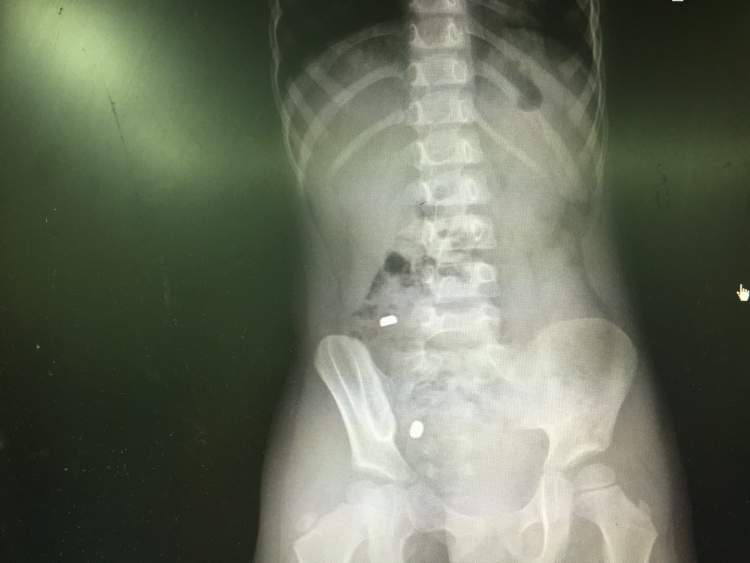

经影像检查——2粒电池已经“抵达”小肠!医生告知家长,电池一旦破损,碱性化学物质泄露,即会灼伤胃肠黏膜,造成出血,甚至穿孔,后果不堪设想。由于电池位于小肠,胃镜技术已经无能为力,需要手术治疗。

情急之下,家长连夜赶赴上海儿童医学中心。经过消化内科进一步定位,确认电池卡在小肠和结肠连接处回盲部位置,这个位置粘膜壁薄,极易穿孔,必须尽快处理。